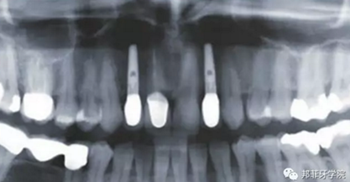

圖2:治療前全景片

牙齦成型器周圍應(yīng)嚴(yán)密縫合,防止唾液進入切口(圖9)。X線片顯示植體位置理想(圖10)。愈合期未見并發(fā)癥,植體周圍牙齦愈合良好(圖11)。十周后取模,椅旁制備臨時牙(圖12),并制作螺絲固位PEEK基臺。

圖 10:拍片復(fù)查植體位置